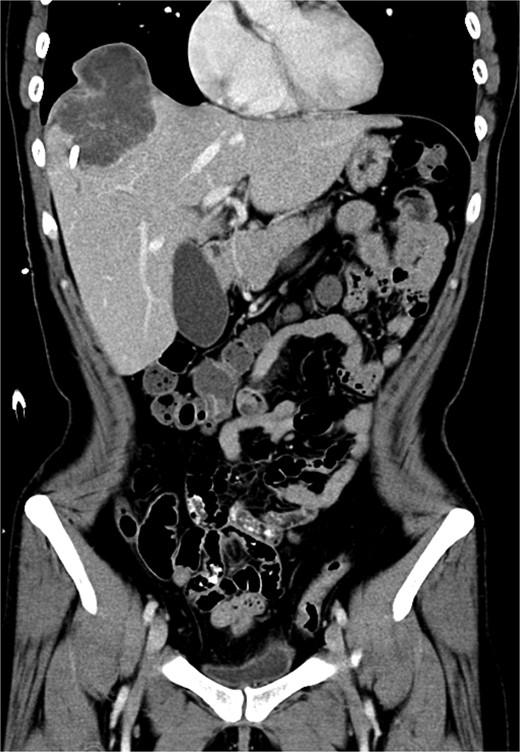

Laparoscopic S8 monosegment liver resection was initiated, including S8 pedicle resection and parenchymal division using an EndoGIA stapler and harmonic scalpel. Due to tumor invasion, the procedure was converted to open. Parenchymal dissection was completed with the harmonic scalpel. Pringle maneuver was employed with total clamping time of 78 minutes. Diaphragm resection and RLL wedge resection were performed (Fig. 4). The diaphragm was repaired with silk sutures. Specimen margins were confirmed to be free of tumor, although tumor rupture at the medial site occurred due to severe adhesion to the diaphragm and RLL. Cholecystectomy and hilum lymph node dissection were also performed. A Jackson-Pratt drain was placed over the cutting surface. A chest tube was placed over right side.